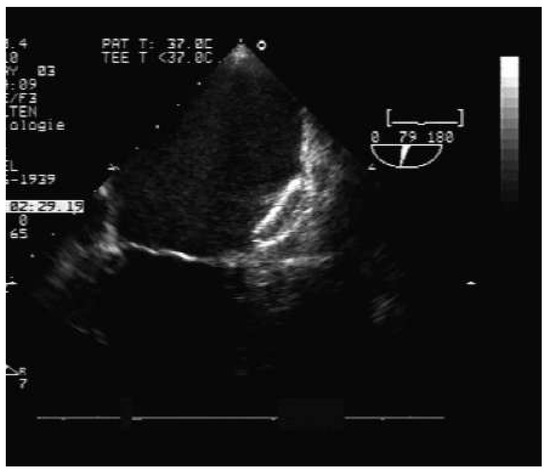

The fact that non-valvular (non-rheumatic) atrial fibrillation creates detectable thrombi in 17% of patients without oral anticoagulation and that 16% of the 17% (over 90% relatively) reside in the left atrial appendage (LAA), suggest that patients w...